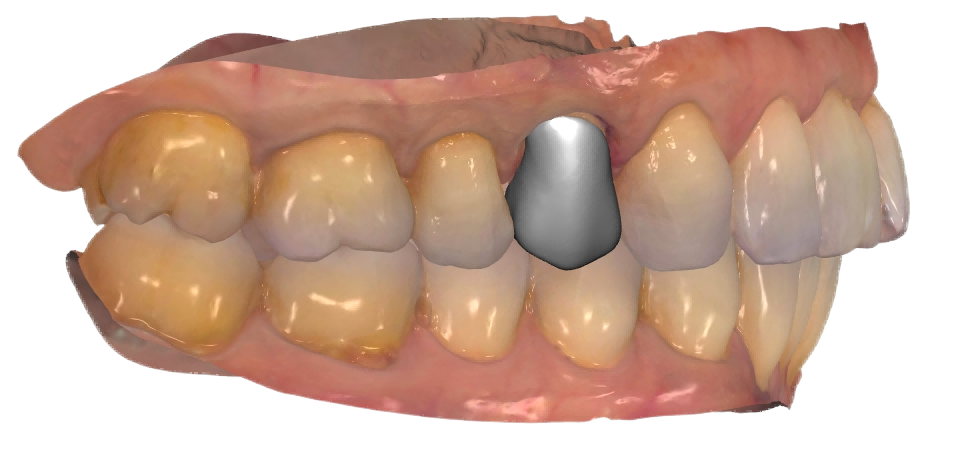

真实案例

TRUE CASE